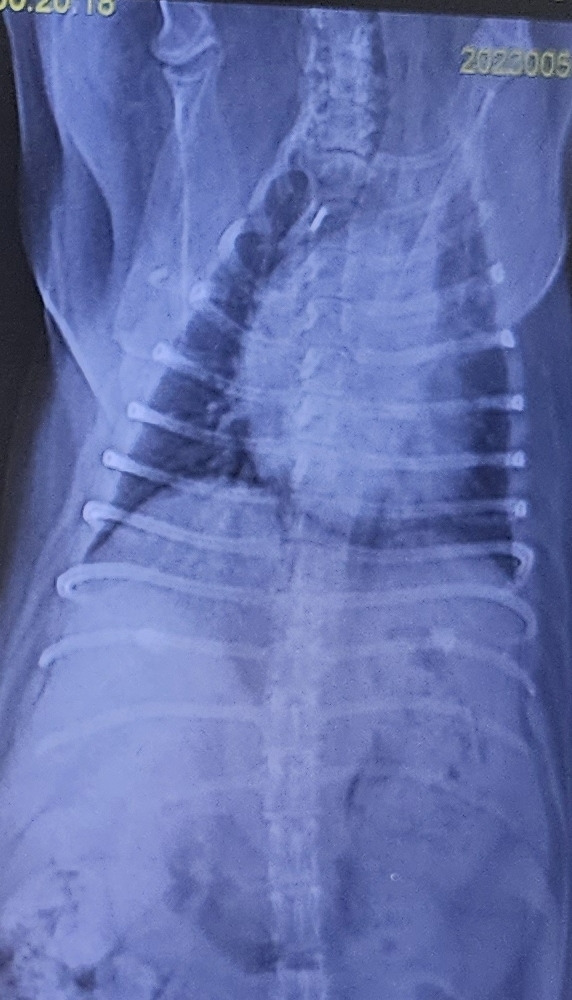

엑스레이 사진(왼쪽)을 보면 물이 많이 차서 심장과 폐를 구분할 수가 없다.

왼쪽 5월 5일 새벽. 오른쪽 5월 5일 오후